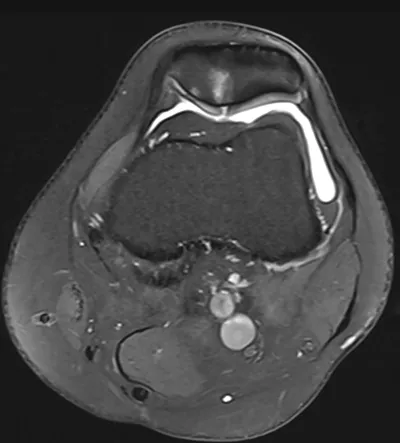

Cartilage Radiology Images

Browse 4 medical images tagged with cartilage. This collection includes various imaging modalities for medical education and reference.

- This collection contains 4 radiology images related to cartilage, including various imaging modalities such as X-rays, MRIs, CT scans, and ultrasound images commonly used in medical diagnosis and education.